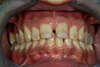

Les colorations dentaires

Tâches fluorose